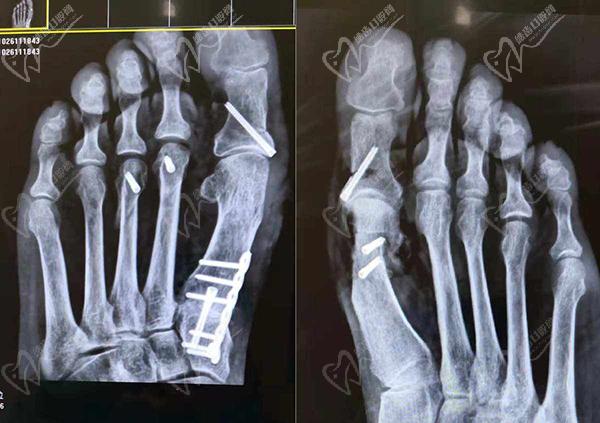

大腳骨微創(chuàng)手術(shù):適合輕中度大腳骨外翻,蘇敬達(dá)大腳骨手術(shù)切口僅需要3-5個(gè)mm就可以做手術(shù),能同時(shí)達(dá)到祛骨贅、復(fù)位關(guān)節(jié)、調(diào)整關(guān)節(jié)囊、收緊韌帶、截骨內(nèi)推、家長足底力線等問題,確保手術(shù)不會復(fù)發(fā)。

大腳骨傳統(tǒng)手術(shù):適合重度大腳骨外翻或合并癥